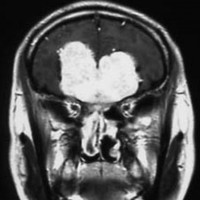

上矢状洞髄膜腫 superior sagittal sinus meningioma

上矢状洞を埋め尽くすように増大して,頭蓋骨浸潤が著しい髄膜腫ですが,ごく軽度の右足脱力以外に何の症状もありません。上矢状洞はゆっくり閉塞すれば,このような頭頂部から後頭部にわたる広範閉塞でも,静脈還流に障害がない場合が多いといえます。大脳の前半部の血流は前頭葉表面の皮質静脈から海綿静脈洞に側副路を形成しています。頭蓋内圧亢進所見もなく,これらはこの髄膜腫がゆっくり増大したということを示唆しています。

手術直後の画像です。全部いっぺんに摘出するのは無理なので,まず前から80%くらいの腫瘍を摘出しました。肥厚した骨はチタンプレートで置き換えてあります。後頭部の上矢状洞内と大脳鎌に少し残りましたが,この6ヶ月後に2回目の開頭術をして全摘出しました。結果的にこの例では,上矢状洞を冠状縫合のあたりから,静脈洞交会まで壁ごと全部摘出しましたが,脳浮腫も何も生じませんでした。腫瘍の両側にある皮質静脈 cortical veinsを損傷しないことが肝要です。

右の病理像は,頭蓋骨浸潤している部分 ですが,骨破壊は良性髄膜腫に特徴的な骨内浸潤像です。この骨浸潤像は悪性像とはいえません。MIB-1は高いところで8%、低いところで3%程度です。